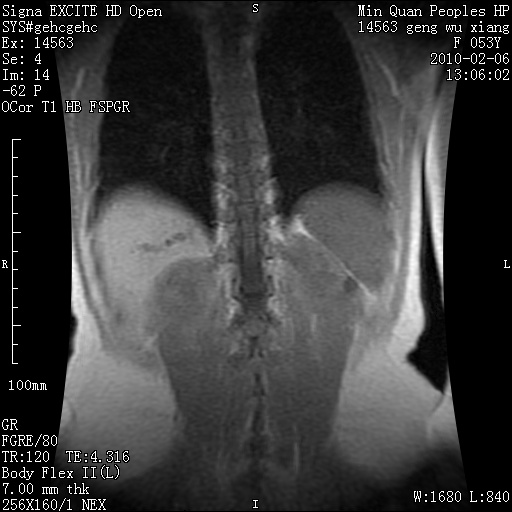

标题: MRI2762:胆道梗阻原因?

f,53y,全身黄染多日。

高位胆道梗阻 胆管癌可能性大

支持 高位胆道梗阻 胆管癌可能性大。